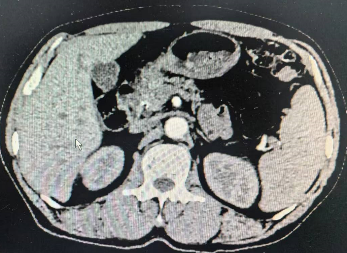

2024年7月CT结果 腹腔肿瘤消失

经过7个多月“漫长的等待”,患者于2024年7月再次入住老年普外科大明宫院区,术前再次行上腹部增强CT结果:胃窦壁稍厚,并浆膜外渗出性改变;横结肠局部壁厚,周围软组织增多,术前分期cTxNxM0,治疗后降期明显,已经符合手术根治性切除标准,如图二的CT所示。术前老年病MDT评估患者情况良好。做好术前准备后在大明宫手术室和麻醉科的配合下,2024年7月23日由科室主任王志东教授主刀,李运浩博士,金鑫住院医师协助进行完全腹腔镜下远端胃癌根治术,手术顺利,术后恢复顺利。术后病理显示胃癌病灶和淋巴结转移完全消失(图四所示),达到了医学上称之为的病理完全缓解(pCR)。知道这个结果后病人和家属都皆大欢喜,悬着的心终于放下了。术后1月来院系统复查仍然未见肿瘤复发和转移迹象,并再次进行了辅助治疗后顺利出院。